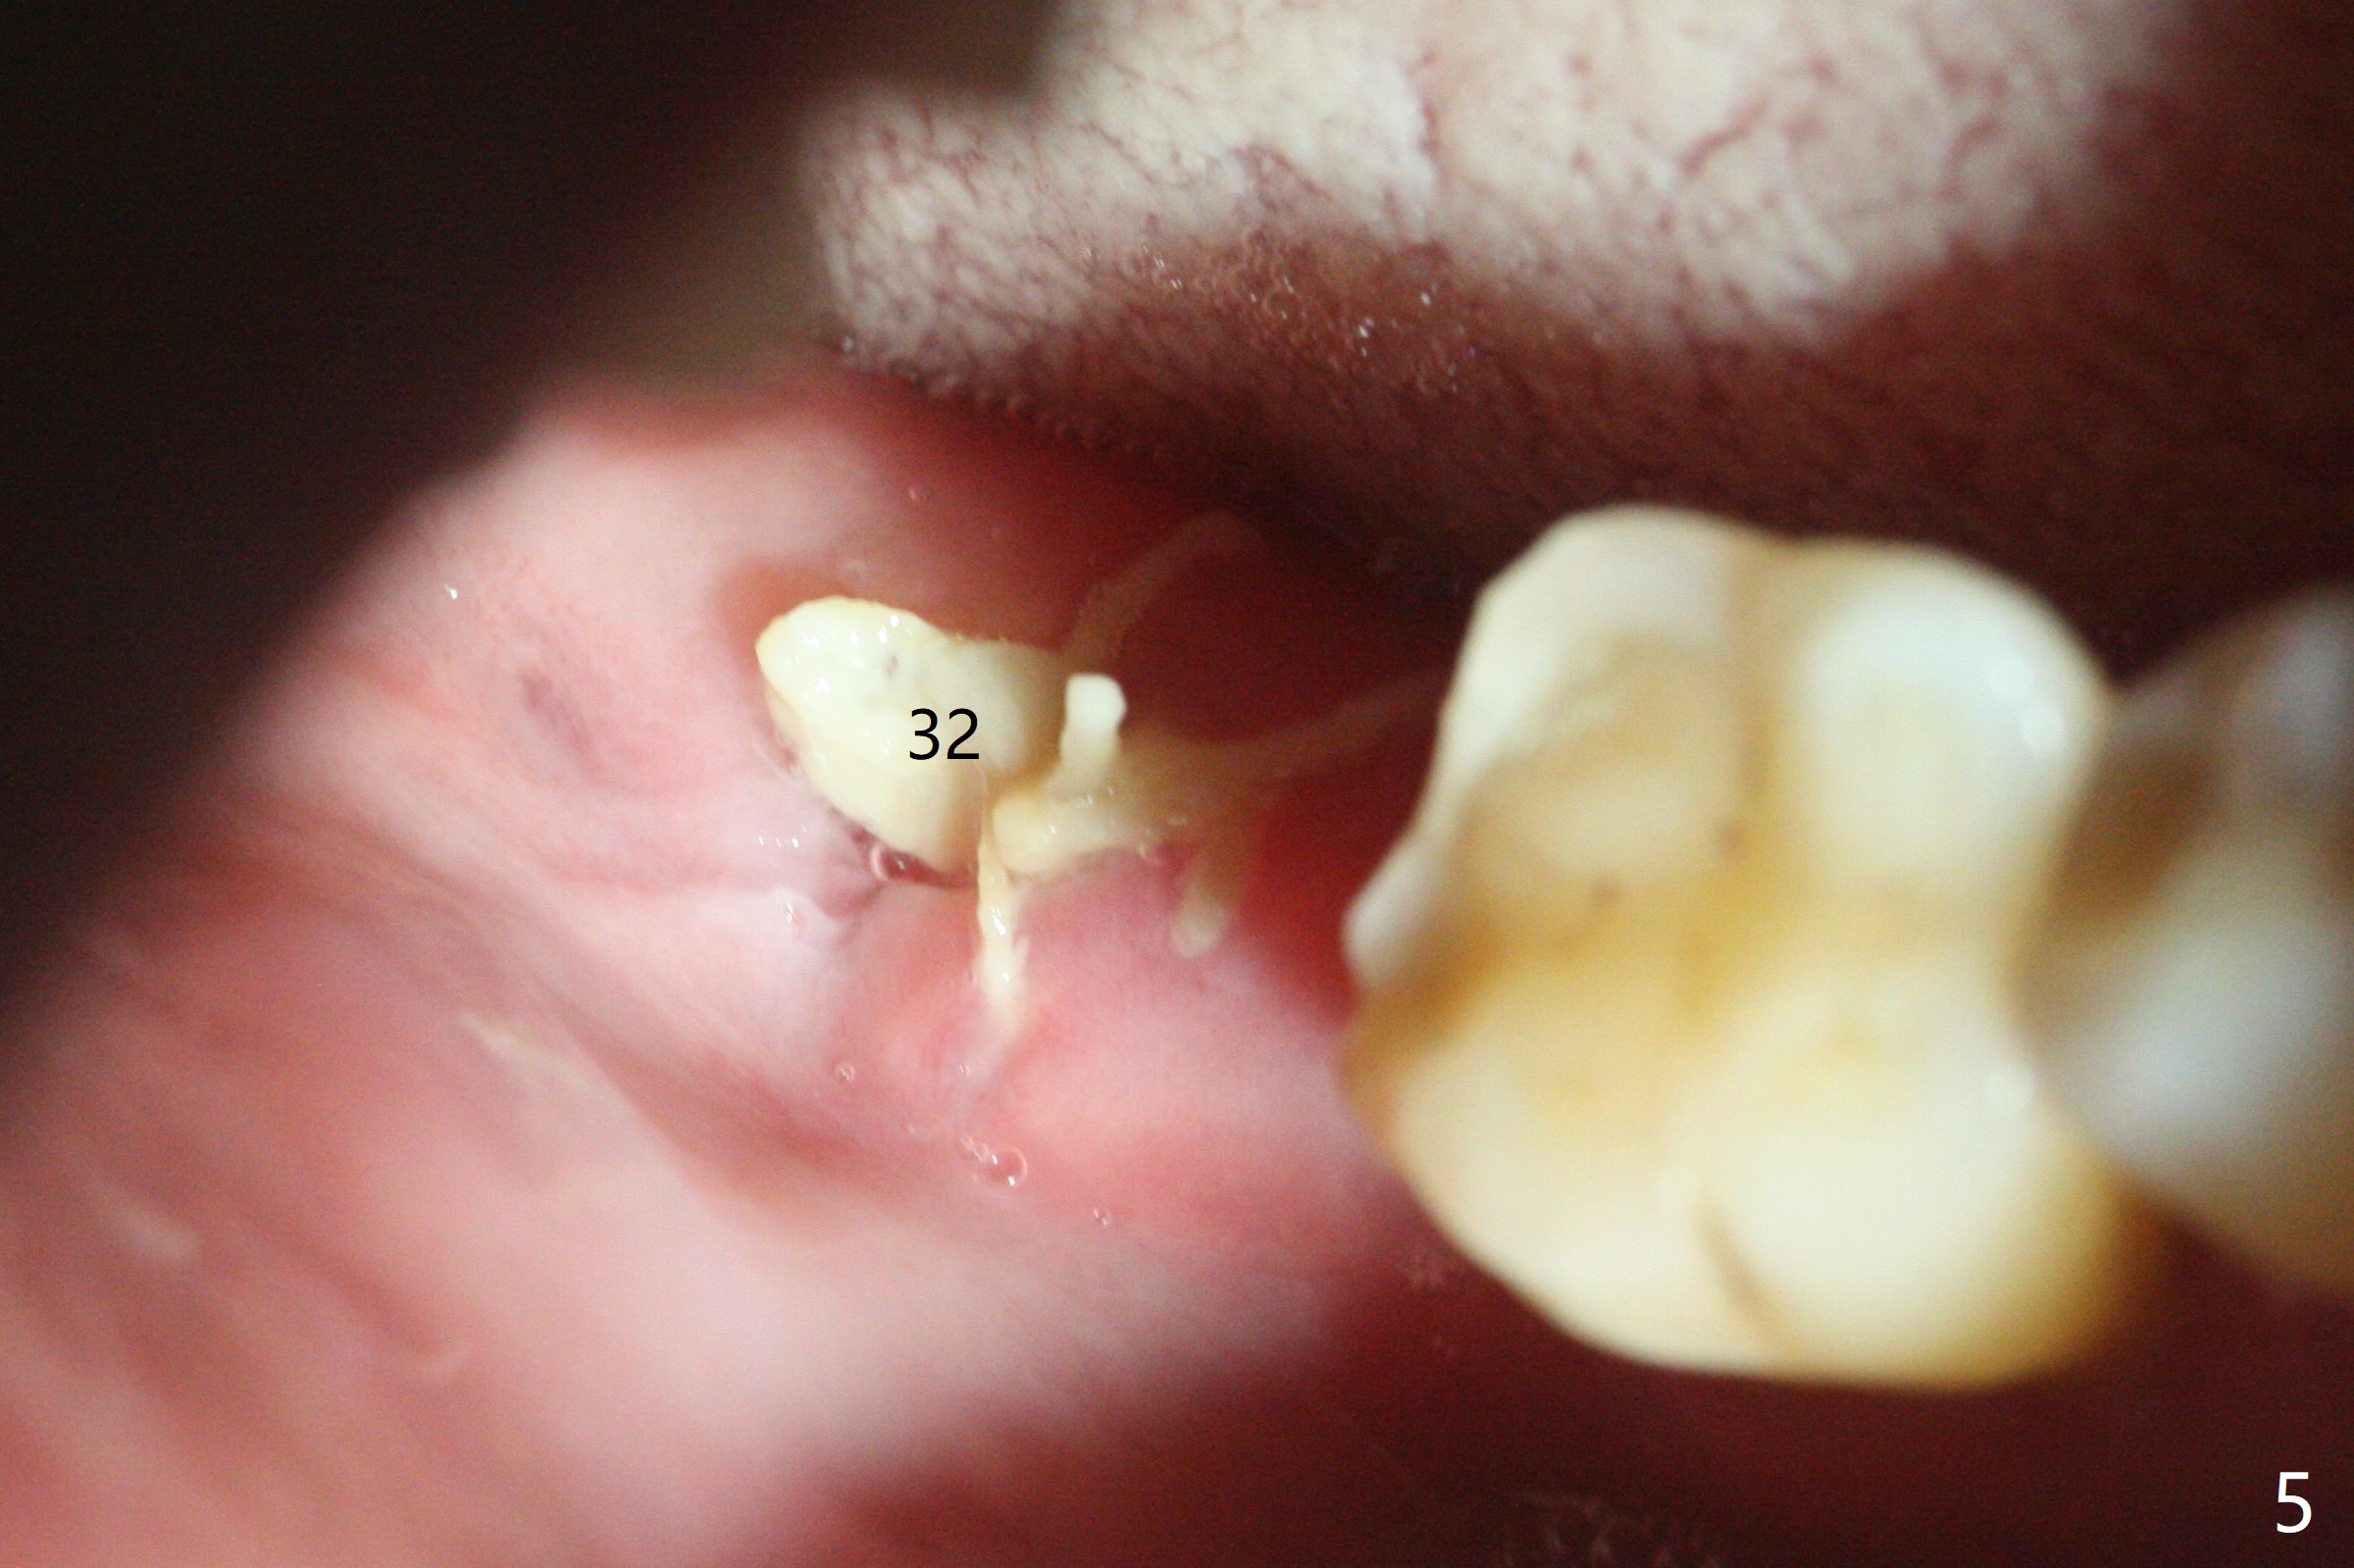

Since the distal crest is low at #19 after extraction (Fig.3), a 4.5x11 mm FC implant (Fig.4 green) will be immediately placed in the mesial socket (lingual), which has more clearance from the Inferior Alveolar Canal (yellow). Sticky bone will be initially up to the implant plateau, followed by insertion of a cemented abutment (pink), placement of the 2nd round of bone graft (red) and fabrication of an immediate provisional (white). To save time, a piece of collagen plug is inserted into the apical portion of the distal socket (blue). The distal crest will be expected to increase ~ 3 mm by the procedure mentioned above. The #32 socket heals with apparent exposure of collagen plug 2 weeks postop (Fig.5). The #27 and 28 sockets heal with fresh granulation tissue 2 weeks postop (Fig.6). The fistula buccal to #28 socket appears to have shrunken 2 weeks postop (Fig.7).